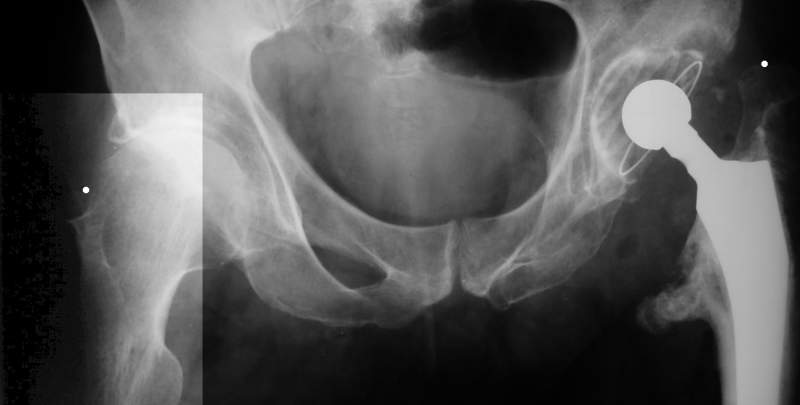

Коллеги, обещанный follow-up.

Больного прооперировали на прошлой неделе (цементный протез, цемент с гентамицином). Использовали задне-боковой доступ. В области перелома подвижности практически не было, так что тему сообщения уместно заменить на "неправильно сросшаяся шейка". И в головке, и во впадине

были значительные дегенеративные изменения, так что ни биполяр, ни остеосинтез тут неуместны (хотя это предлагали в ortopod'е). После релиза удлинили ногу на 3 см. Дальше удлинять побоялись из-за

натяжения седалищного нерва, хотя в принципе можно было бы еще 15-20 мм нарастить. По послеоперационной рентгенограмме анатомическое укорочение порядка 15 мм. Клинически при ходьбе - 4 см, но это за счет перекоса таза.

The patient underwent cemented THR on last week. Postero-lateral approach was used. There was only minimal motion at the fracture site and we had to cut the femoral head with oscillating saw. The femoral head was deformed with it's cartilage completely absent in some areas.

Acetabulum showed gross degenerative changes, especially in superior rim. So I think it was right choice not to do ORIF in this case. After some soft tissue release we've lengthened the leg up to 3 cm. Further lengthening was possible but we stopped at that moment due to tension of n. ischiadicus. Now patient walks with crutches. Leg length discrepancy is about 4 cm due to pelvic tilt (discrepancy on post-op x-ray is 15 mm).